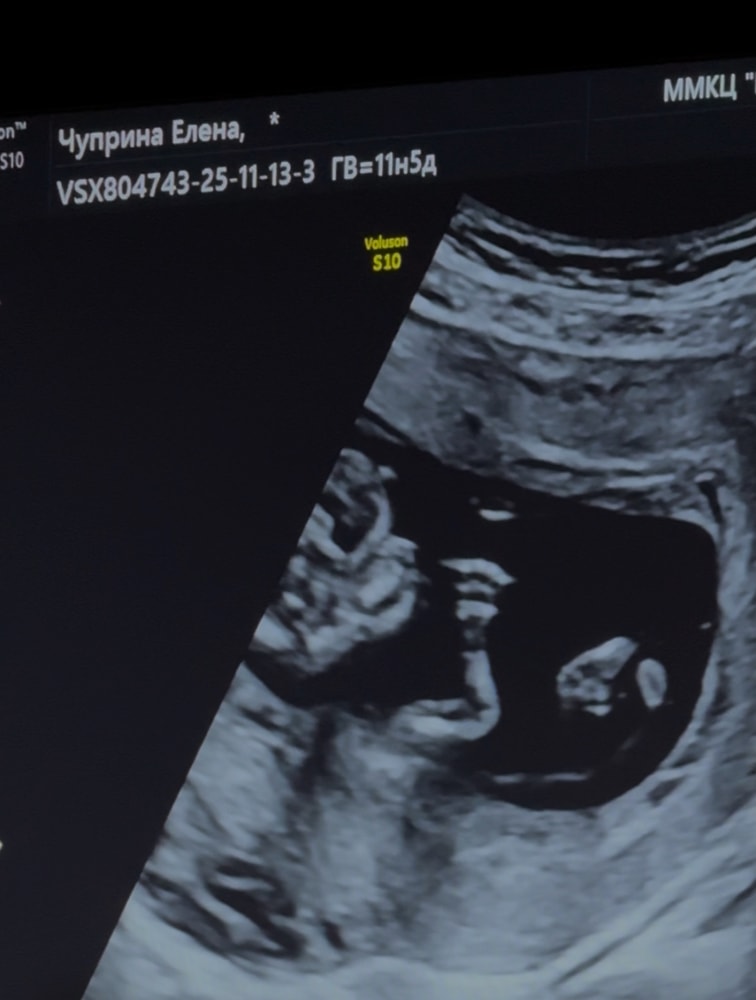

Личико!🥹🥹🥹 Хоспадеееее, я уже не в том возрасте такие киношки смотреть💔🥹😂

Результаты УЗИВолнение и первые слова врача: «Плод есть, сердцебиение есть». Выдыхаешь сразу😅 Последний раз была на УЗИ 5 недель назад, когда малыш совсем крошечный был. А сегодня прям человек! Эти ножки, махающая ручка, личико🥹на меня похожа кроха (внизу фото)😁